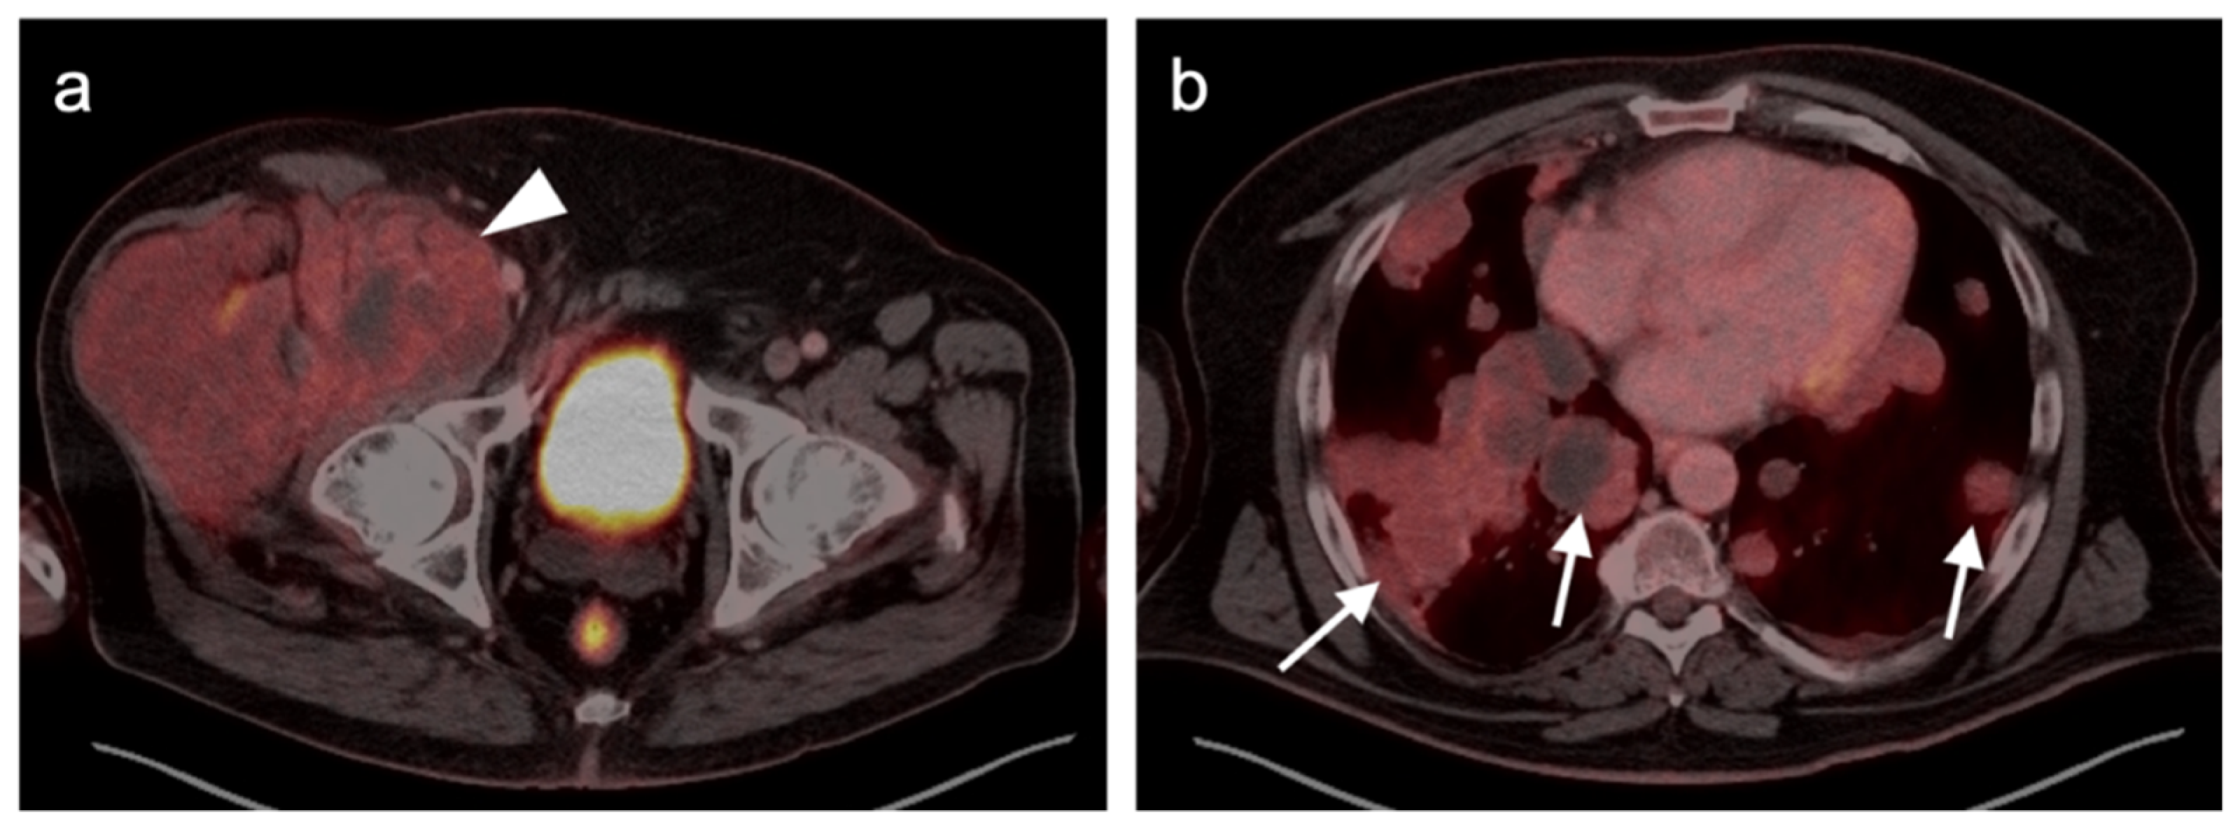

- Gao, Y.-J.; Yang, Z.; Yu, J.-Y.; Li, N.; Wang, X.-J.; Zhou, N.-N. Potential application value of PET/computed tomography in retroperitoneal leiomyosarcoma and a literature review. Nucl. Med. Commun. 2021, 42, 800–810. [Google Scholar] [CrossRef]

- Subramaniam, S.; Callahan, J.; Bressel, M.; Hofman, M.S.; Mitchell, C.; Hendry, S.; Vissers, F.L.; Van der Hiel, B.; Patel, D.; Van Houdt, W.J.; et al. The role of 18 F-FDG PET/CT in retroperitoneal sarcomas—A multicenter retrospective study. J. Surg. Oncol. 2021, 123, 1081–1087. [Google Scholar] [CrossRef]